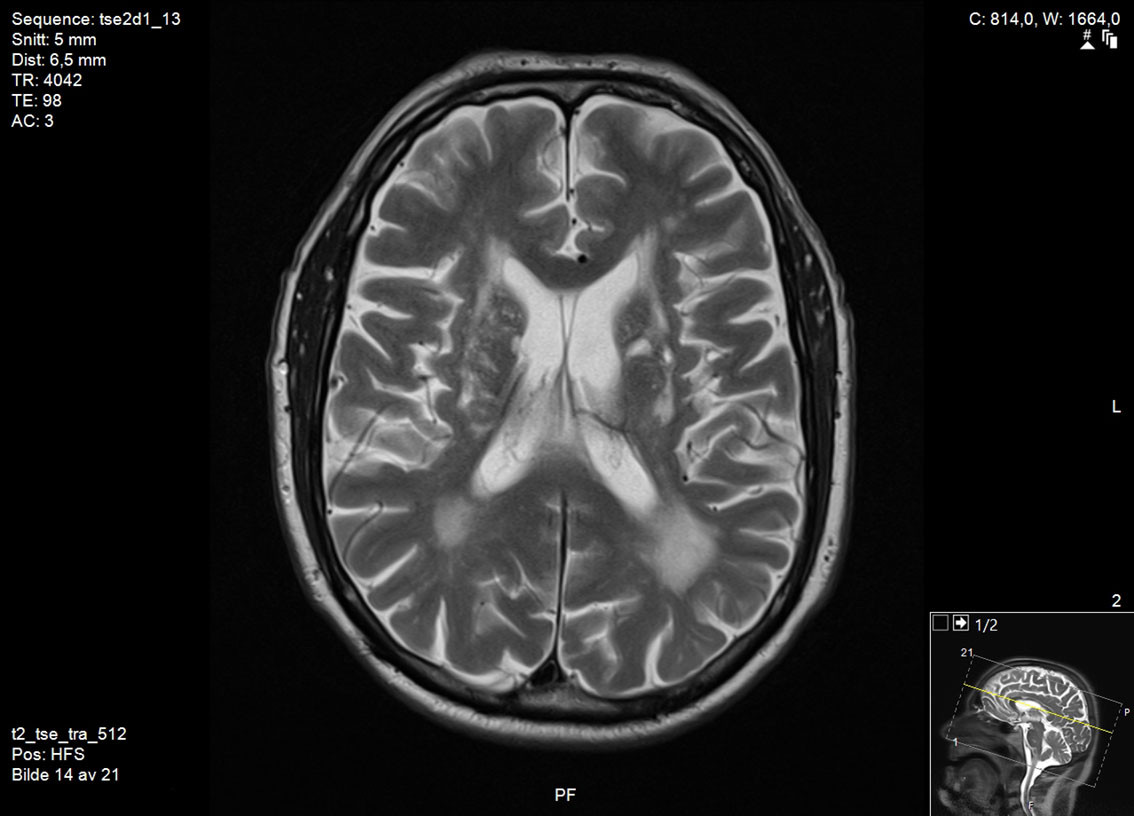

There are no universally accepted guidelines for the diagnosis of vascular parkinsonism, but based on clinical findings and pathology, Zijlmans et al. have proposed the following criteria: a) parkinsonism, b) cerebrovascular disease visible on MRI or CT, and c) a relation between a) and b), either in the form of acute hemiparkinsonism resulting from infarction or haemorrhage in the nigrostriatal pathway (subtype 1), or small vessel disease in the white matter with gradual development of parkinsonism (subtype 2) (15). Typically, brain MRI is necessary to determine whether there is damage to the nigrostriatal pathway (Figure 1) or small vessel disease in the white matter (Figure 2). CT scans of the brain are less suitable for making the diagnosis due to their lower sensitivity for lacunar infarcts and small vessel disease (5).

Differences between vascular parkinsonism and Parkinson's disease are also seen on brain imaging. In cases of vascular parkinsonism, brain MRI will reveal infarction, haemorrhage, or signs of small vessel disease. In Parkinson's disease, brain MRI can appear completely normal, although elderly patients may have vascular changes as incidental findings; however, these will be much less abundant than in cases of vascular parkinsonism (20, 21). A dopamine transporter scan (DaTSCAN) is a nuclear medicine procedure that shows changes in brain dopaminergic activity, and that can be used to detect degeneration of nigrostriatal nerve endings. DaTSCAN always shows pathological changes in Parkinson's disease, whereas in cases of vascular parkinsonism DaTSCAN is often normal if the nigrostriatal pathway is not directly affected (5).